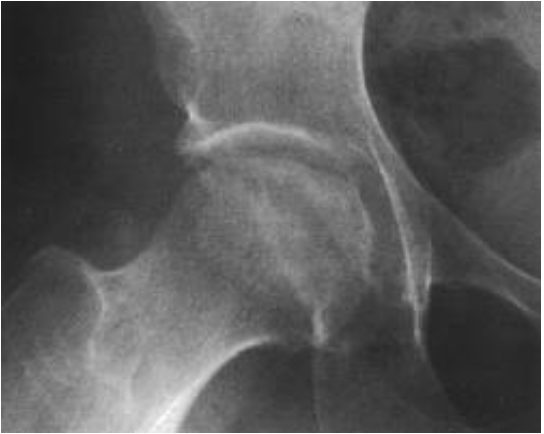

Вывих ТБС. Головка бедренной кости смещена и выходит на пределы вертлужной впадины.

Перелом. Имеет вид линии или щели. Чаще всего располагается в области шейки бедренной кости.

Остеопороз. Проявляется видимым снижением плотности костной ткани. На рентгенограммах принимает вид участков затемнения.

Некроз. Участок некроза кажется более плотным, из-за чего выделяется на фоне окружающих тканей.

Деструкция. На рентгенограмме имеет вид костного дефекта. Свежие деструктивные очаги имеют неровные контуры, застарелые – ровные и уплотненные.

Деформирующий остеоартроз. На ранних стадиях рентгенологические признаки отсутствуют. Позже о патологии говорит сужение суставной щели.